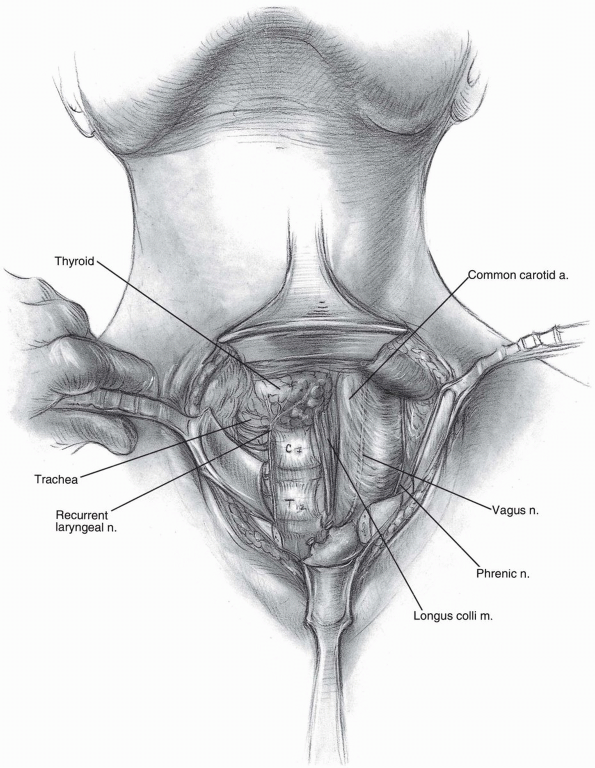

Direct Anterior Cervical Thoracic Approach

This is a modification of the anterior exposure with

resection of the medial clavicle. This approach employs the interval

between the strap muscles medially the sternocleidomastoid laterally,

the esophagus and trachea medially and the carotid sheath laterally.

Selection of a right or left approach is based on familiarity of the

surgeon and recognition that the recurrent laryngeal nerve is more

consistent on the left side than on the right side of the neck.

Further, hand dominance, familiarity, and the left sided lymphatic duct

all contribute to the decisions of a left or right approach.

Technique

Once the anterior neck approach is

developed and the pharynx is identified and recurrent laryngeal nerve

typically deep to it. The inferior extent of this anterior dissection

will be the C-7 T-1 disc where upon a more extensile approach is

typically needed (Fig. 13-6). -

Isolation and direct visualization of the

recurrent laryngeal nerve as it enters the tracheoesophageal group is

necessary to avoid transecting this structure (Fig. 13-8). -

The subclavian vein and phrenic nerve are readily identified and followed directly down to the spine (see Fig. 13-8).